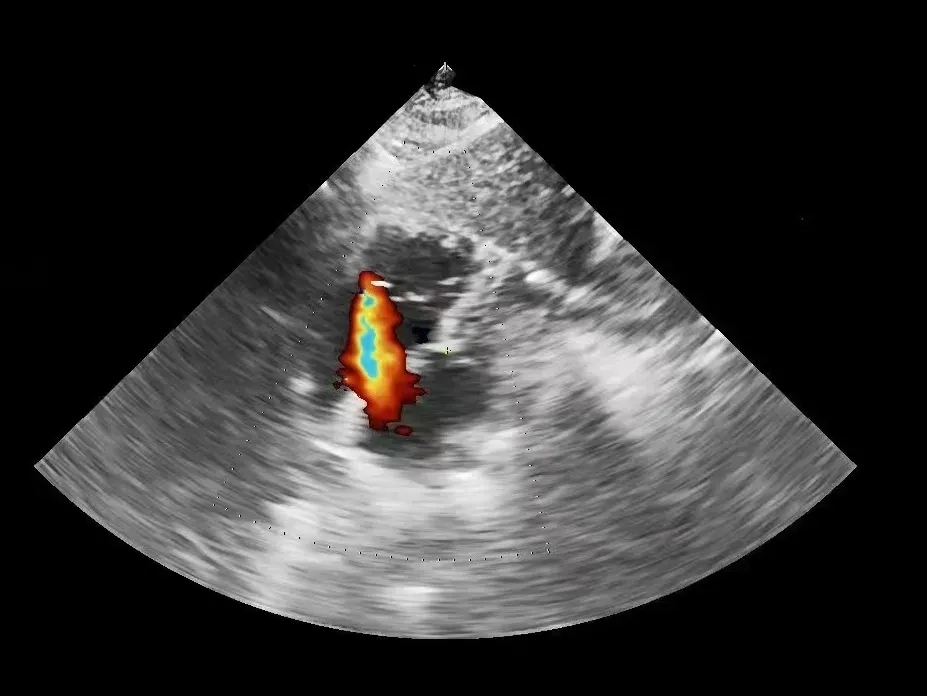

多普勒下可见房水平左向右分流

超声下观察封堵器,左右盘面在房间隔两侧,彩超下无残余分流

多普勒观察封堵器成型后无残余分流

多普勒观察无残余分流